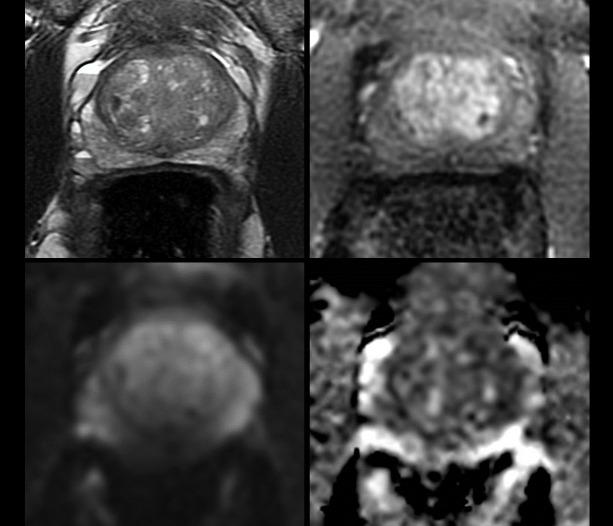

前列腺 MRI 质量:PI-QUAL 评分在前列腺癌诊断中的临床影响。

Prostate MRI quality: clinical impact of the PI-QUAL score in prostate cancer diagnostic work-up.

To assess the reproducibility and impact of prostate imaging quality (PI-QUAL) scores in a clinical cohort undergoing prostate multiparametric MRI.

RESULTS

Image quality was sufficient (≥PI-QUAL-3) in 237/247 (96%) and optimal (≥PI-QUAL-4) in 206/247 (83%) of males undergoing 3T-MRI. Overall PI-QUAL scores showed moderate inter-reader agreement for senior ( = 0.51) and junior-senior readers ( = 0.47), with DCE showing highest agreement ( = 0.47). With PI-QUAL-5 studies, the negative MRI calls increased from 50 to 87% and indeterminate PI-RADS-3 rates decreased from 31.8. to 10.4% compared to lower quality PI-QUAL-3 studies. More patients with PI-QUAL scores 1-3 underwent biopsy for negative (47%) and indeterminate probability (100%) MRIs compared to PI-QUAL score 4-5 (30 and 75%, respectively). Ability to rule-in cancer increased with PI-QUAL score, from 50% at PI-QUAL 1-2 to 90% for PI-QUAL 4-5, with a similarly, but greater effect for ruling-out cancer and at a lower threshold, from 0% for scans of PI-QUAL 1-2 to 67.1% for PI-QUAL 4 and 100% for PI-QUAL-5.

CONCLUSION

Higher PI-QUAL scores for image quality are associated with decreased uncertainty in MRI decision-making and improved efficiency of diagnostic pathway delivery.